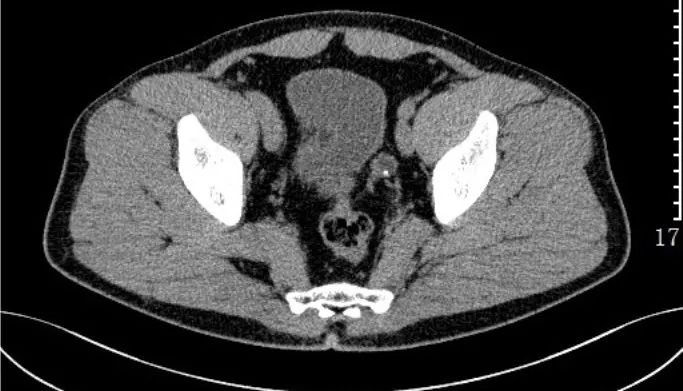

7)肝硬化:是临床常见的慢性进行性肝病,由一种或多种病因长期或反复作用形成的弥漫性肝损害。临床上以肝功能损害和门脉高压症为主要表现,并有多系统受累。

CT表现:肝叶比例失调,肝脏表面高低不平,肝裂增宽,肝脏密度不均匀;继发性改变:脾肿大,腹水,门脉高压(侧支循环形成,脾门、胃底、食管下段静脉迂曲扩张)。